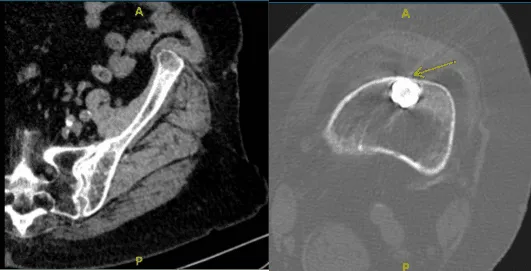

A las 6 semanas de la primera visita, el paciente regresó con el resultado de una tomografía computarizada, que fue revisada y descartó nuestro pinzamiento, y había cambios degenerativos leves en la cadera izquierda y presenta enfermedad aterosclerótica.

También se encontró que la punta distal del fémur impacta la corteza anterior del fémur con erosión. Hablamos sobre opciones de tratamiento, incluyendo quirúrgico y no quirúrgico.